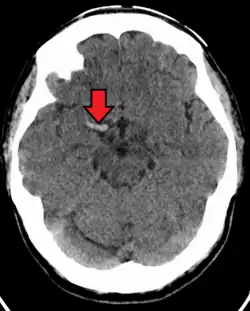

Cerebral venous sinus thrombosis

Cerebral venous sinus thrombosis (CVST) is a rare form of stroke which results from the blockage of the dural venous sinuses by a thrombus. Symptoms may include headache, abnormal vision, any of the symptoms of stroke such as weakness of the face and limbs on one side of the body and seizures. The diagnosis is usually made with a CT or MRI scan. The majority of persons affected make a full recovery. The mortality rate is 4.3%.[15]